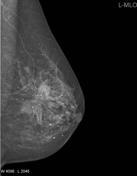

First Mammogram

Friday marked my first mammogram since my diagnosis. I had one (well 2) on the day I was diagnosed but Friday was my first one since. As I have an implant reconstruction on my left side where I had my mastectomy I will only have mammograms on my right boob. I will now have yearly mammograms until I am 50 and will then join the regular breast screening programme (only 21 years to go!👵). Personally I don't find mammograms too bad pain wise, it's just a squished boob for a couple of seconds while the Radiographer takes an x-ray, shuffle into another position then same again. I have seen a debate on whether the pain some people get is to do with boob size but apparently its just an individual pain tolerance thing and how sensitive your boobs are to the squishing - nothing to do with how much the Radiographers are squishing as the pressure is measured although this may be something I will have to update you on once I spend some time on placement in Mammography which I am due to do in year 2! I'll pop some x-ray images below of the mammogram x-ray machine and the x-rays produced (it wouldn't be one of my blogs without something a bit sciencey 🤓) so you can see the pretty pictures they produce.

The image on the left is called a Medio-Lateral Oblique (MLO) view and is the 'side to side' view whereas the image on the right is called a Cranio-Caudal view and is the 'top to bottom' view. In Radiography we always try get 2 x-rays at 90 degrees to each other! In the middle you can see the machine that squished my boob - boob goes on the black shelf and they pop different sized paddles above to flatten it out.